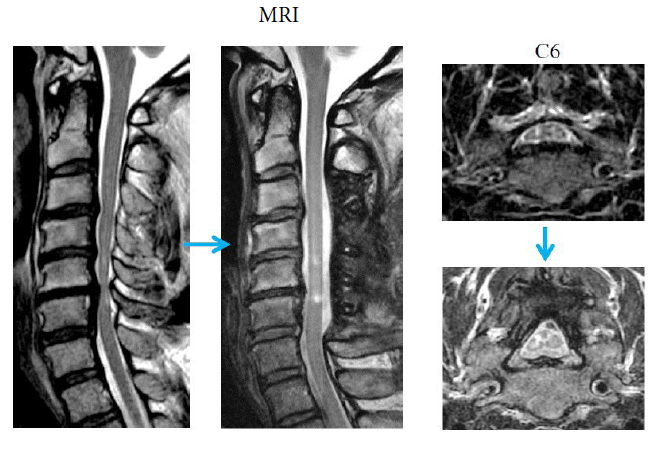

Figure 9: Sagittal and axial sections (C6 level) of MRI. Before surgery and after surgery.

The spinal cord was completely decompressed after surgery.